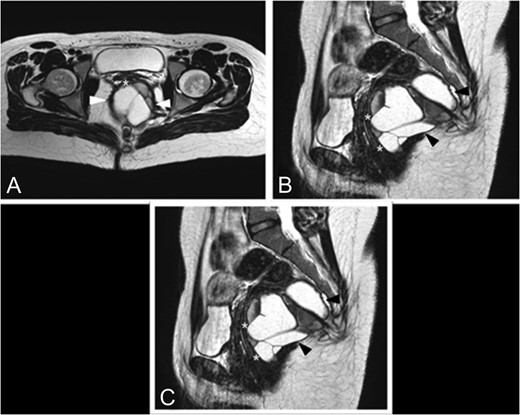

MRI (Magnetic Resonance Imagery) and endorectal-US revealed a wide, homogeneous, multiloculated cystic lesion (8.8 × 8.3 × 10 cm3). The mass lay on the right posterolateral pararectal space, in an extraperitoneal plan, following the course of the rectal distal portion in the context of the levator ani muscle. At IV contrast injection scans no significant contrast agent uptake by the lesion was detected (Fig. 1A–C).

Preoperative MRI. (A) Axial TSE T2-weighted images show a large multiloculated cystic lesion (arrowhead) dislocating and closely adherent to the posterior rectal wall (*). (B) This sagittal TSE T2-weighted image shows a cystic lesion (arrowhead) expanded in the posterior pararectal space, containing serum-proteinaceous material, following the course of the rectal distal portion (*) in the context of the levator ani muscle. (C) Coronal TSE T2-weighted images demostrate the relations among the cystic lesion (black*), the rectum (white*) and the levator ani muscle (arrowhead).